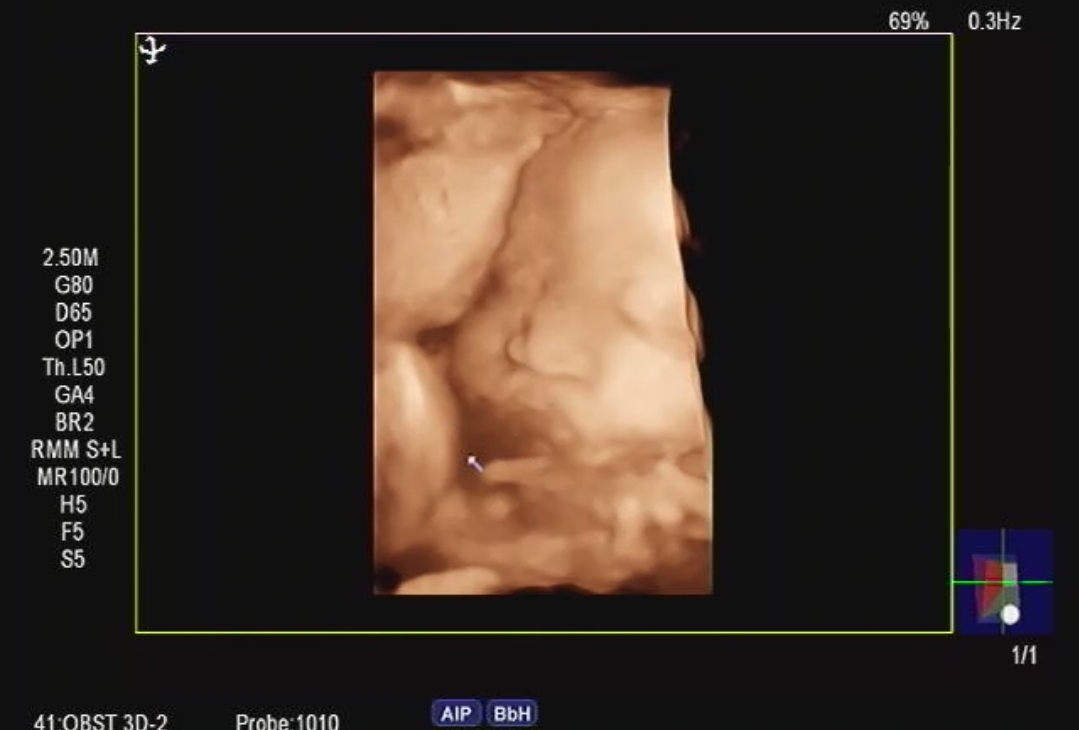

드디어 얼굴보기 성공!!

37주만에 아기가 얼굴을 보여줬네요ㅠㅠ 그동안에는 맨날 등돌려있고 손으로 열심히 가려서 매번 못보고왔는데,, 이렇게 출산을 앞두고 보여주다니,,♡ 넘 사랑스러워서 오늘 하루종일 사진만 보고있어요 ㅋㅋㅋㅋ팔불출 혹시 저처럼 아직 못보신분들도 희망을 가져보시길바래용ㅎ!!